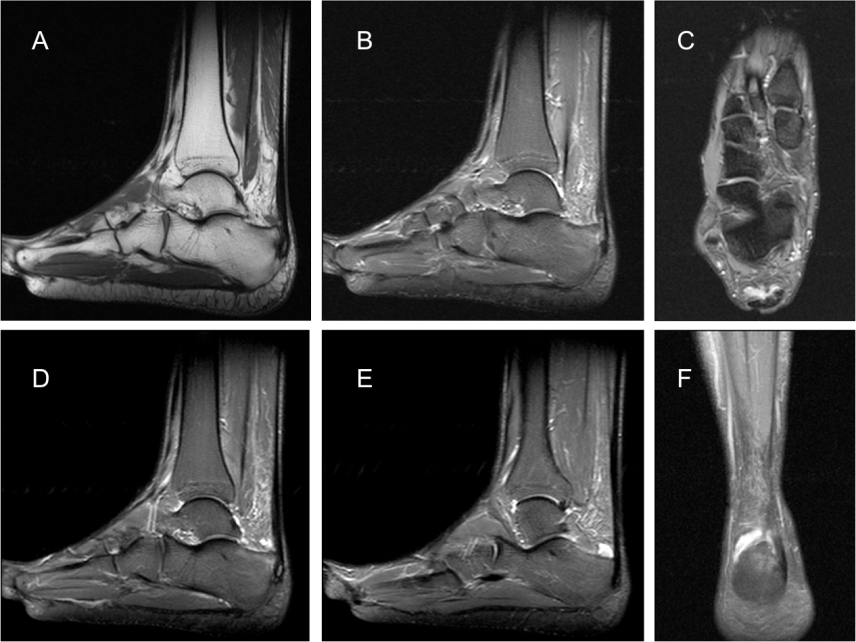

- Perdida / afectación del espacio de Kager por la bursitis retrocalcánea

- Tendinosis aquílea. El tendon mide más de 9 mm.

- Aumento de partes blandas. Se observa una convexidad de tejidos blandas posterior al Aquiles por la burisitis superficial.

Resonancia Magnética:

- Engrosamiento focal y alteración de señal en la inserción del tendón de aquiles al calcáneo.

- Bursitis retrocalcánea y rotroaquílea.

- Edema de médula ósea en la tuberosidad calcánea.